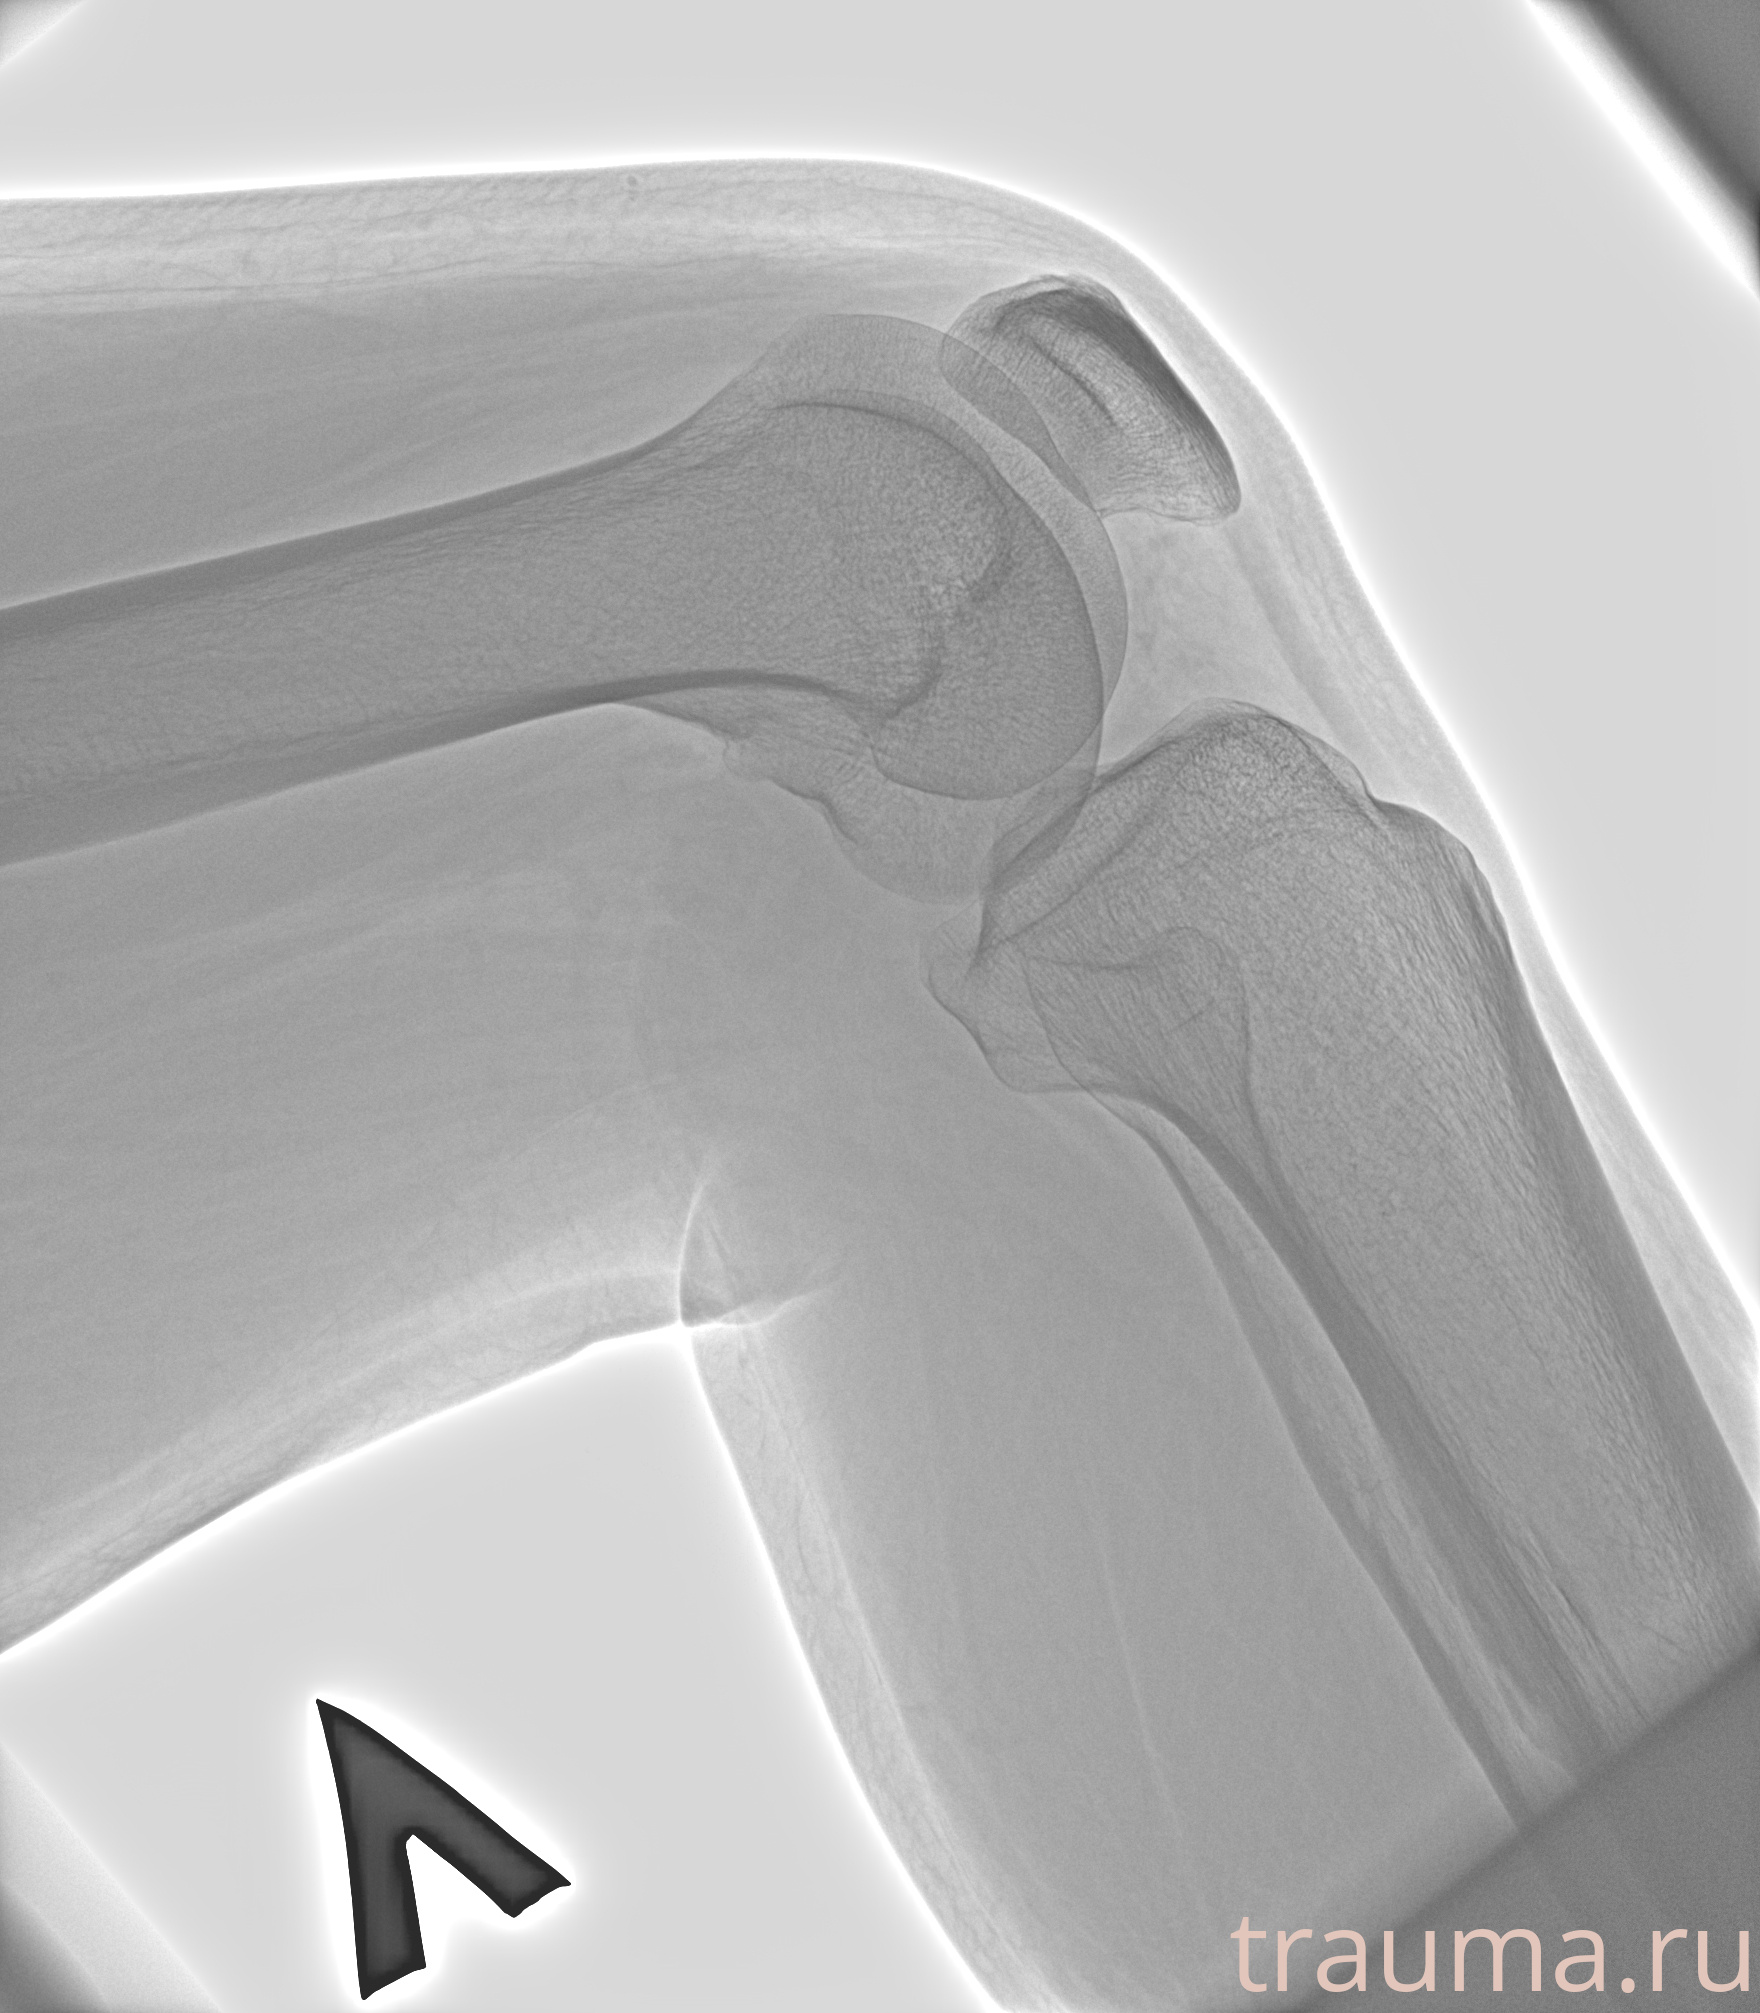

Рентгенограммы